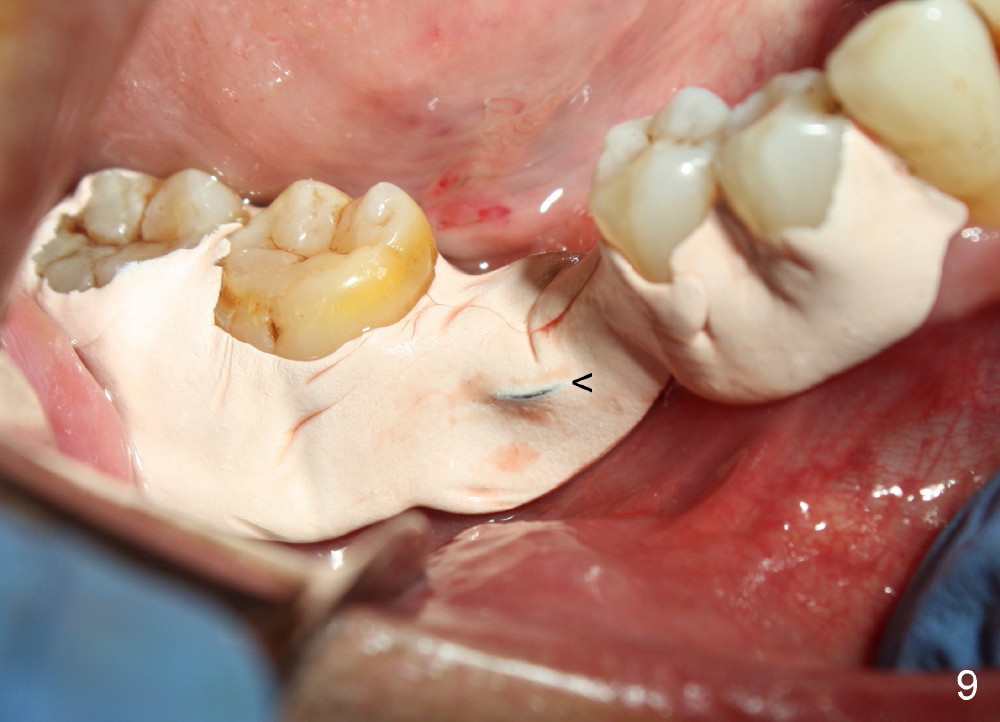

When a positioning pin is placed in the osteotomy with 10 mm deep, the sensor cannot be placed deep enough because of pin interference so no IAC is visible (Fig.4). When the pin is removed and the sensor is placed low enough, IAC is clearly shown, but the osteotomy is barely visible (Fig.5 pink dashed line). With information obtained from pre- (Fig.2,3) and intra- (Fig.4,5) op PA, twelve mm of osteotomy appears to be appropriate. A final implant (5.3x12 mm) is placed with separation from IAC (Fig.6, insertion torque 50 Ncm). A healing abutment is placed (Fig.7,8), which helps retain perio dressing (Fig.9). Two weeks later, the gingiva heals around the abutment (Fig.10). Four months postop, the implant appears to osteointegrate (Fig.11). A cemented abutment is placed (Fig.12). With supragingival margin, oral hygiene is easily maintained (Fig.13). Due to delayed placement, the gingival embrasure is extremely large (*). The issue is much less with immediate implant.